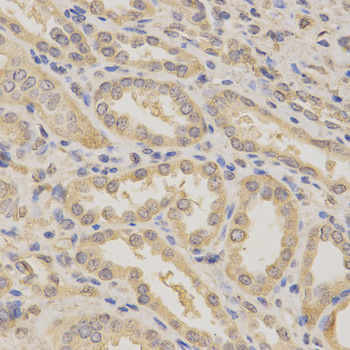

Immunohistochemistry of paraffin-embedded colon cancer using BCL2L1 antibody.

Immunohistochemistry of paraffin-embedded human kidney using BCL2L1 antibody at dilution of 1:200 (x400 lens)